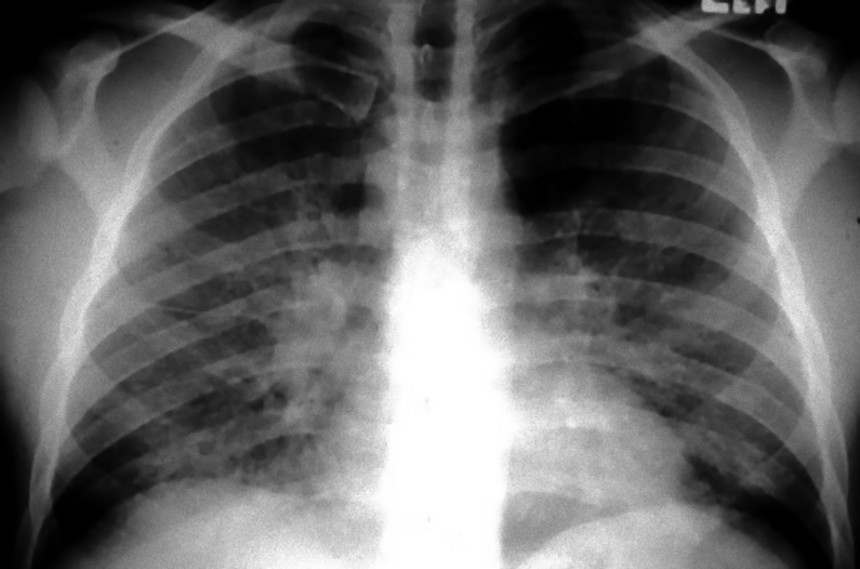

5. 結核の治療に革命

この画像を大きなサイズで見る20年代半ばに抗生物質が登場するまで、結核を治すには療養所で休むしかないと考えられていた。治療は早期発見が決め手とされていたが、従来の胸の音を聴く方法では正確な診断が難しかった。だが、レントゲン写真の登場によって、結核菌が肺に作り出した特徴的な影を確認できるようになった。また、軍や工場、炭鉱においてもレントゲン写真が導入され、結果として多くの命が救われた。